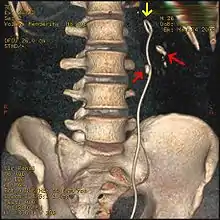

Most stones under 5 mm (0.2 in) pass spontaneously.[32][7] Prompt surgery may, nonetheless, be required in persons with only one working kidney, bilateral obstructing stones, a urinary tract infection and thus, it is presumed, an infected kidney, or intractable pain.[111] Beginning in the mid-1980s, less invasive treatments such as extracorporeal shock wave lithotripsy, ureteroscopy, and percutaneous nephrolithotomy began to replace open surgery as the modalities of choice for the surgical management of urolithiasis.[7] More recently, flexible ureteroscopy has been adapted to facilitate retrograde nephrostomy creation for percutaneous nephrolithotomy. This approach is still under investigation, though early results are favorable.[112] Percutaneous nephrolithotomy or, rarely, anatrophic nephrolithotomy, is the treatment of choice for large or complicated stones (such as calyceal staghorn calculi) or stones that cannot be extracted using less invasive procedures.[56][7]

Ureteroscopic surgery

Ureteroscopy has become increasingly popular as flexible and rigid fiberoptic ureteroscopes have become smaller. One ureteroscopic technique involves the placement of a ureteral stent (a small tube extending from the bladder, up the ureter and into the kidney) to provide immediate relief of an obstructed kidney. Stent placement can be useful for saving a kidney at risk for postrenal acute kidney failure due to the increased hydrostatic pressure, swelling and infection (pyelonephritis and pyonephrosis) caused by an obstructing stone. Ureteral stents vary in length from 24 to 30 cm (9.4 to 11.8 in) and most have a shape commonly referred to as a "double-J" or "double pigtail", because of the curl at both ends. They are designed to allow urine to flow past an obstruction in the ureter. They may be retained in the ureter for days to weeks as infections resolve and as stones are dissolved or fragmented by ESWL or by some other treatment. The stents dilate the ureters, which can facilitate instrumentation, and they also provide a clear landmark to aid in the visualization of the ureters and any associated stones on radiographic examinations. The presence of indwelling ureteral stents may cause minimal to moderate discomfort, frequency or urgency incontinence, and infection, which in general resolves on removal. Most ureteral stents can be removed cystoscopically during an office visit under topical anesthesia after resolution of urolithiasis.[113] Research is currently uncertain if placing a temporary stent during ureteroscopy leads to different outcomes than not placing a stent in terms of number of hospital visits for post operative problems, short or long term pain, need for narcotic pain medication, risk of UTI, need for a repeat procedure or narrowing of the ureter from scarring.[114]